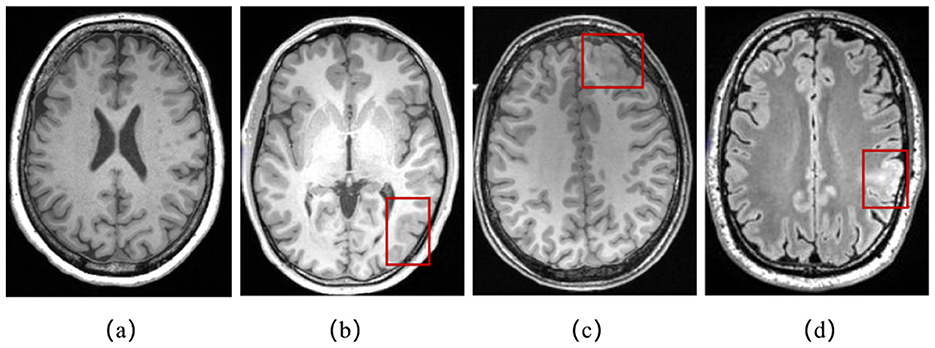

In clinical diagnosis, physicians can identify FCD lesions by analyzing neuroimaging results. Magnetic Resonance Imaging (MRI) is a medical imaging technique that uses the principles of nuclear magnetic resonance to produce detailed images of the internal structures of the human body. On MRI scans, characteristic manifestations of FCD include increased cortical thickness, blurring of the gray/white matter junction, the presence of a transmantle sign, abnormal cortical folding pattern, and increased signal intensity on FLAIR/T2-weighted MRI (Urbach et al., 2022) as depicted in Figure 1. Positron Emission Tomography (PET) is a nuclear medicine imaging technique used to observe biological processes and functional activities within the human body. Between seizures, PET images using fluorodeoxyglucose show hypometabolism in areas of gray matter tissue that are associated with the epileptogenic region (Baete et al., 2004). However, the identification of FCD lesions in clinical practice remains a formidable challenge. Firstly, FCD lesions are often subtle, exhibit diverse morphological features, and possess poorly defined edge, making them difficult to detect through routine visual inspection. Secondly, the analysis of high-resolution 3D imaging datasets is time-consuming, requires specialized expertise, and can be subjective in certain cases. Therefore, there is an urgent need for precise and efficient computational techniques to assist in the localization of FCD lesions.

Figure 1. (a) A T1-weighted MRI slice of normal brain; (b) abnormal gray matter thickening in a T1-weighted MRI slice in red box; (c) blurred junction of gray and white matter in a T1-weighted MRI slice in red box; (d) increased signal intensity in FLAIR in red box.